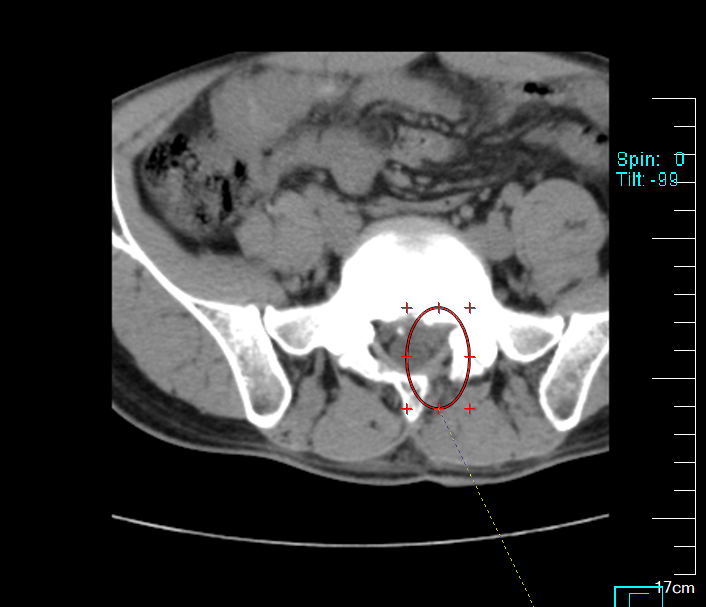

术后

术后次日,舒先生已能戴腰围下床缓慢行走,左下肢放射痛基本消失。“本以为今年要在床上躺过去了,没想到还能站着过年。”他的笑容,成为这个春节前最生动的康复注脚。